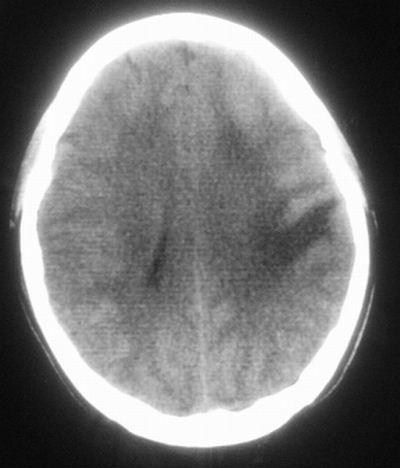

患者,男,30岁,右侧面部麻木,右上肢活动受限27小时。pe:神清、呼吸平稳,口角左歪,右上肢活动受限,右手掌握力消失,右侧躯体痛觉减退。

第一次颅脑ct扫描:左侧额顶叶血肿。

治疗三天后复查ct:除左侧额顶叶血肿外。左侧额叶另见片状低密度灶,密度不均匀,境界不清;考虑脑梗塞。

建议:必要时行进一步检查排除烟雾病。

左侧额顶叶血肿伴出血后梗塞!

支持,建议进一步检查排除血管畸形(动脉瘤 等)

低密度区应该不是梗塞而是水肿区,建议进一步检查排除占位